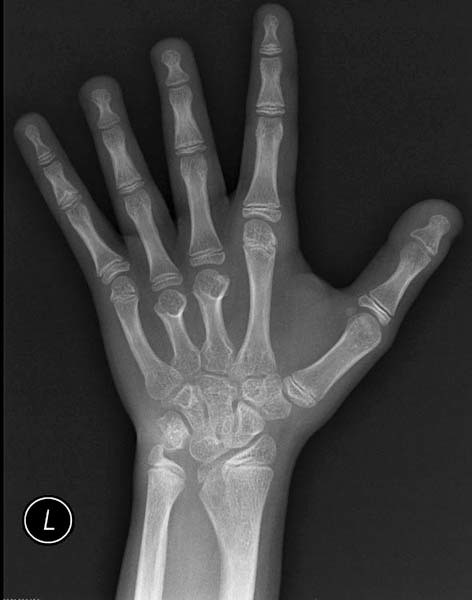

Характерные признаки заболевания: укорочение кисти и низкий рост у пациентки пубертатного возраста

Укорочение кисти за счет костей ладони — характерный признак заболевания - ультразвуковое исследование почек для выявления аномалий развития;

Более редкими признаками в данном случае являются птоз, очень низкая линия роста волос на шее сзади, большое количество пигментных невусов, очень короткие четвертые пястная и плюсневая кости, особая форма подушечек пальцев – они выступают и имеют завитки на кончиках пальцев. Также может проявляться гипоплазия ногтей и вальгусное отклонение в локтевом суставе.

- деформация ушей, локтевых суставов, укорочение пястных костей;